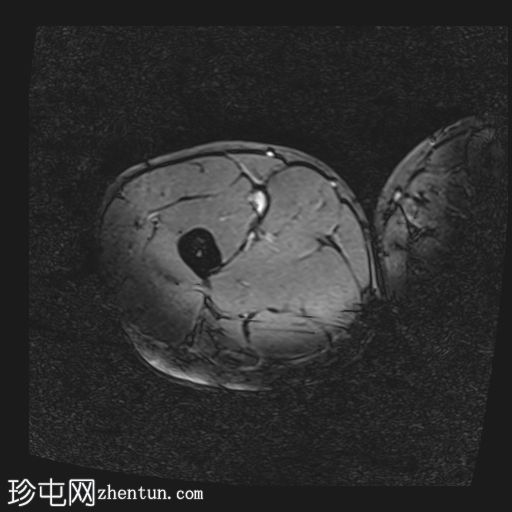

轴位

T2-fl2d-hemo

内收长肌和内收短肌中远侧外侧可见羽状改变和肌内水肿,主要累及内收大肌,长15厘米,宽4厘米。未见明显血肿或完全性肌纤维撕裂。

后腱膜、邻近神经血管交界处及邻近肌间隙可见积液,少量积液向外侧扩散,沿肌间隙到达大腿中远侧。

内收肌腱完整,骨性附着点清晰可见,肌腱轻度增厚,中部可见腱周水肿;未见撕裂。

影像学特征符合英国田径肌肉损伤分级(BAMIC/BAC)2B级损伤,主要累及大收肌。未见明显的血肿或肌纤维完全撕裂。

后侧腱膜、邻近神经血管束及肌间隙可见积液,少量积液沿肌间隙向外侧延伸至大腿中远端。